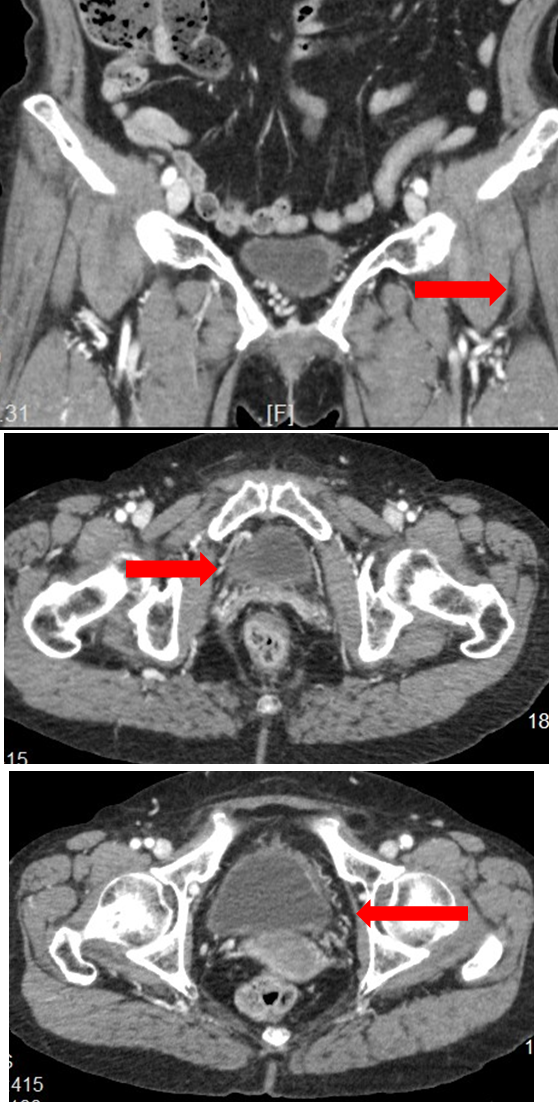

★ Case 1

女性, 28岁,小腿浅静脉曲张就诊

CTV提示双侧卵巢静脉及盆腔静脉扩张迂曲显著

观察、随访处理

无盆腔症状的盆腔源性静脉曲张传统“三明治”